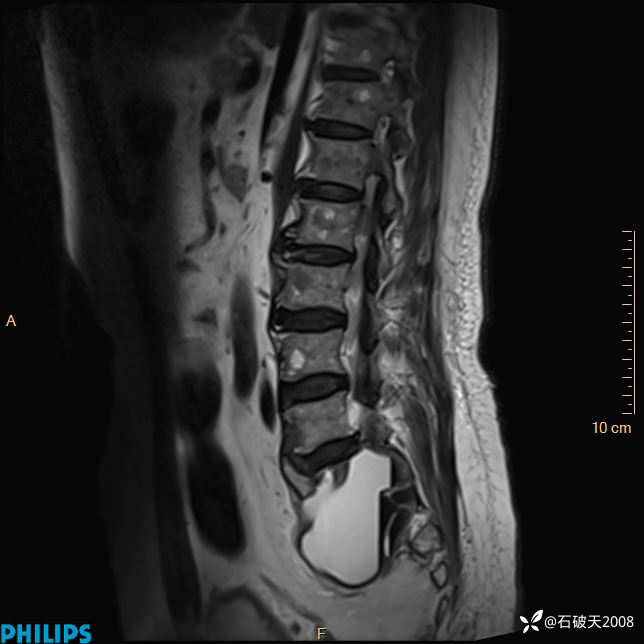

2023年3月份MRI影像

T2矢状位压脂